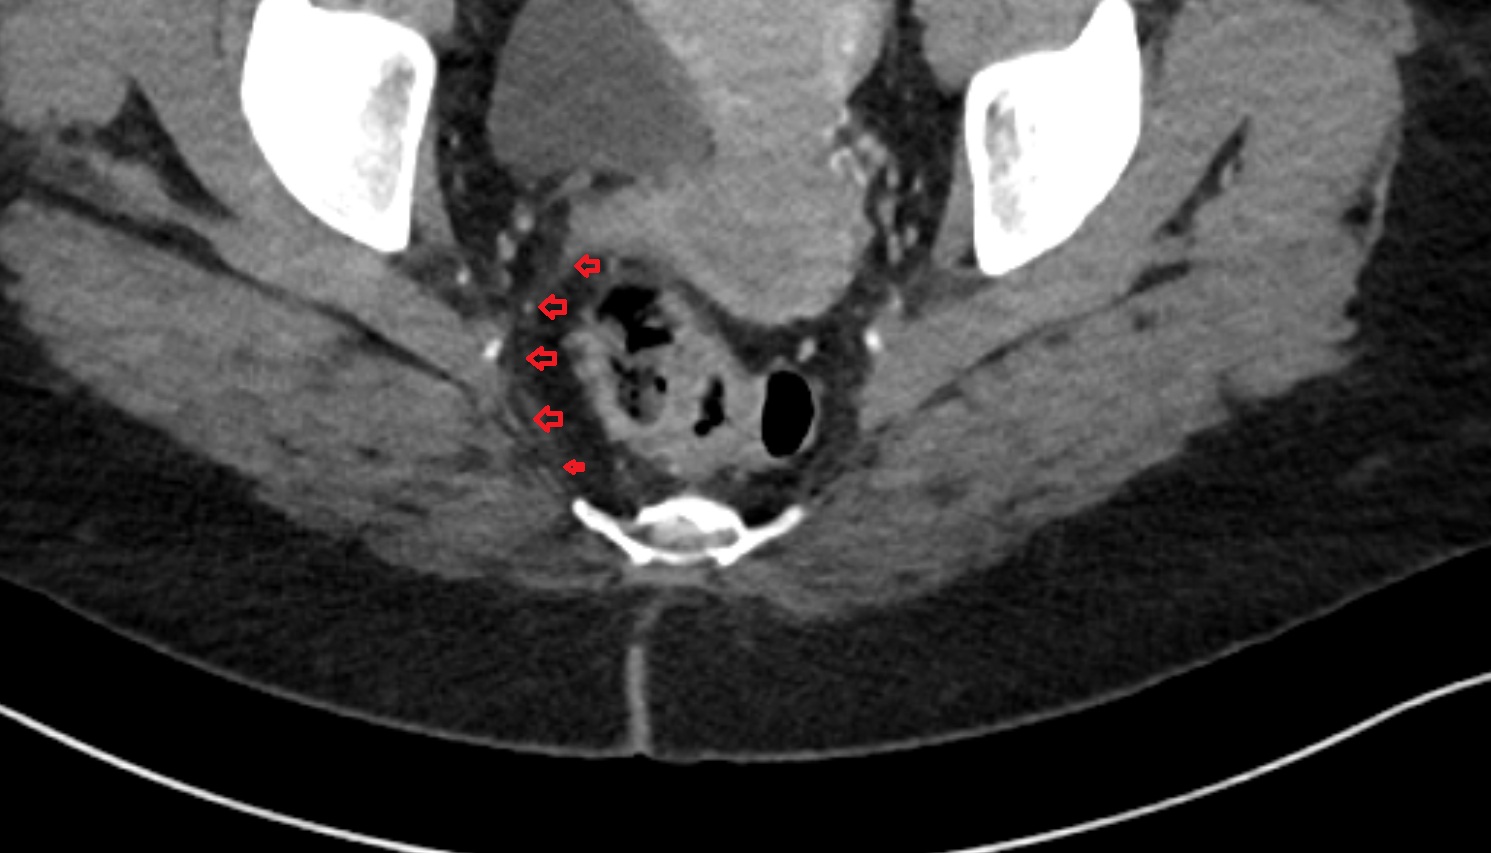

- Mesorectal fascia

- Mesorectum

- Rectum